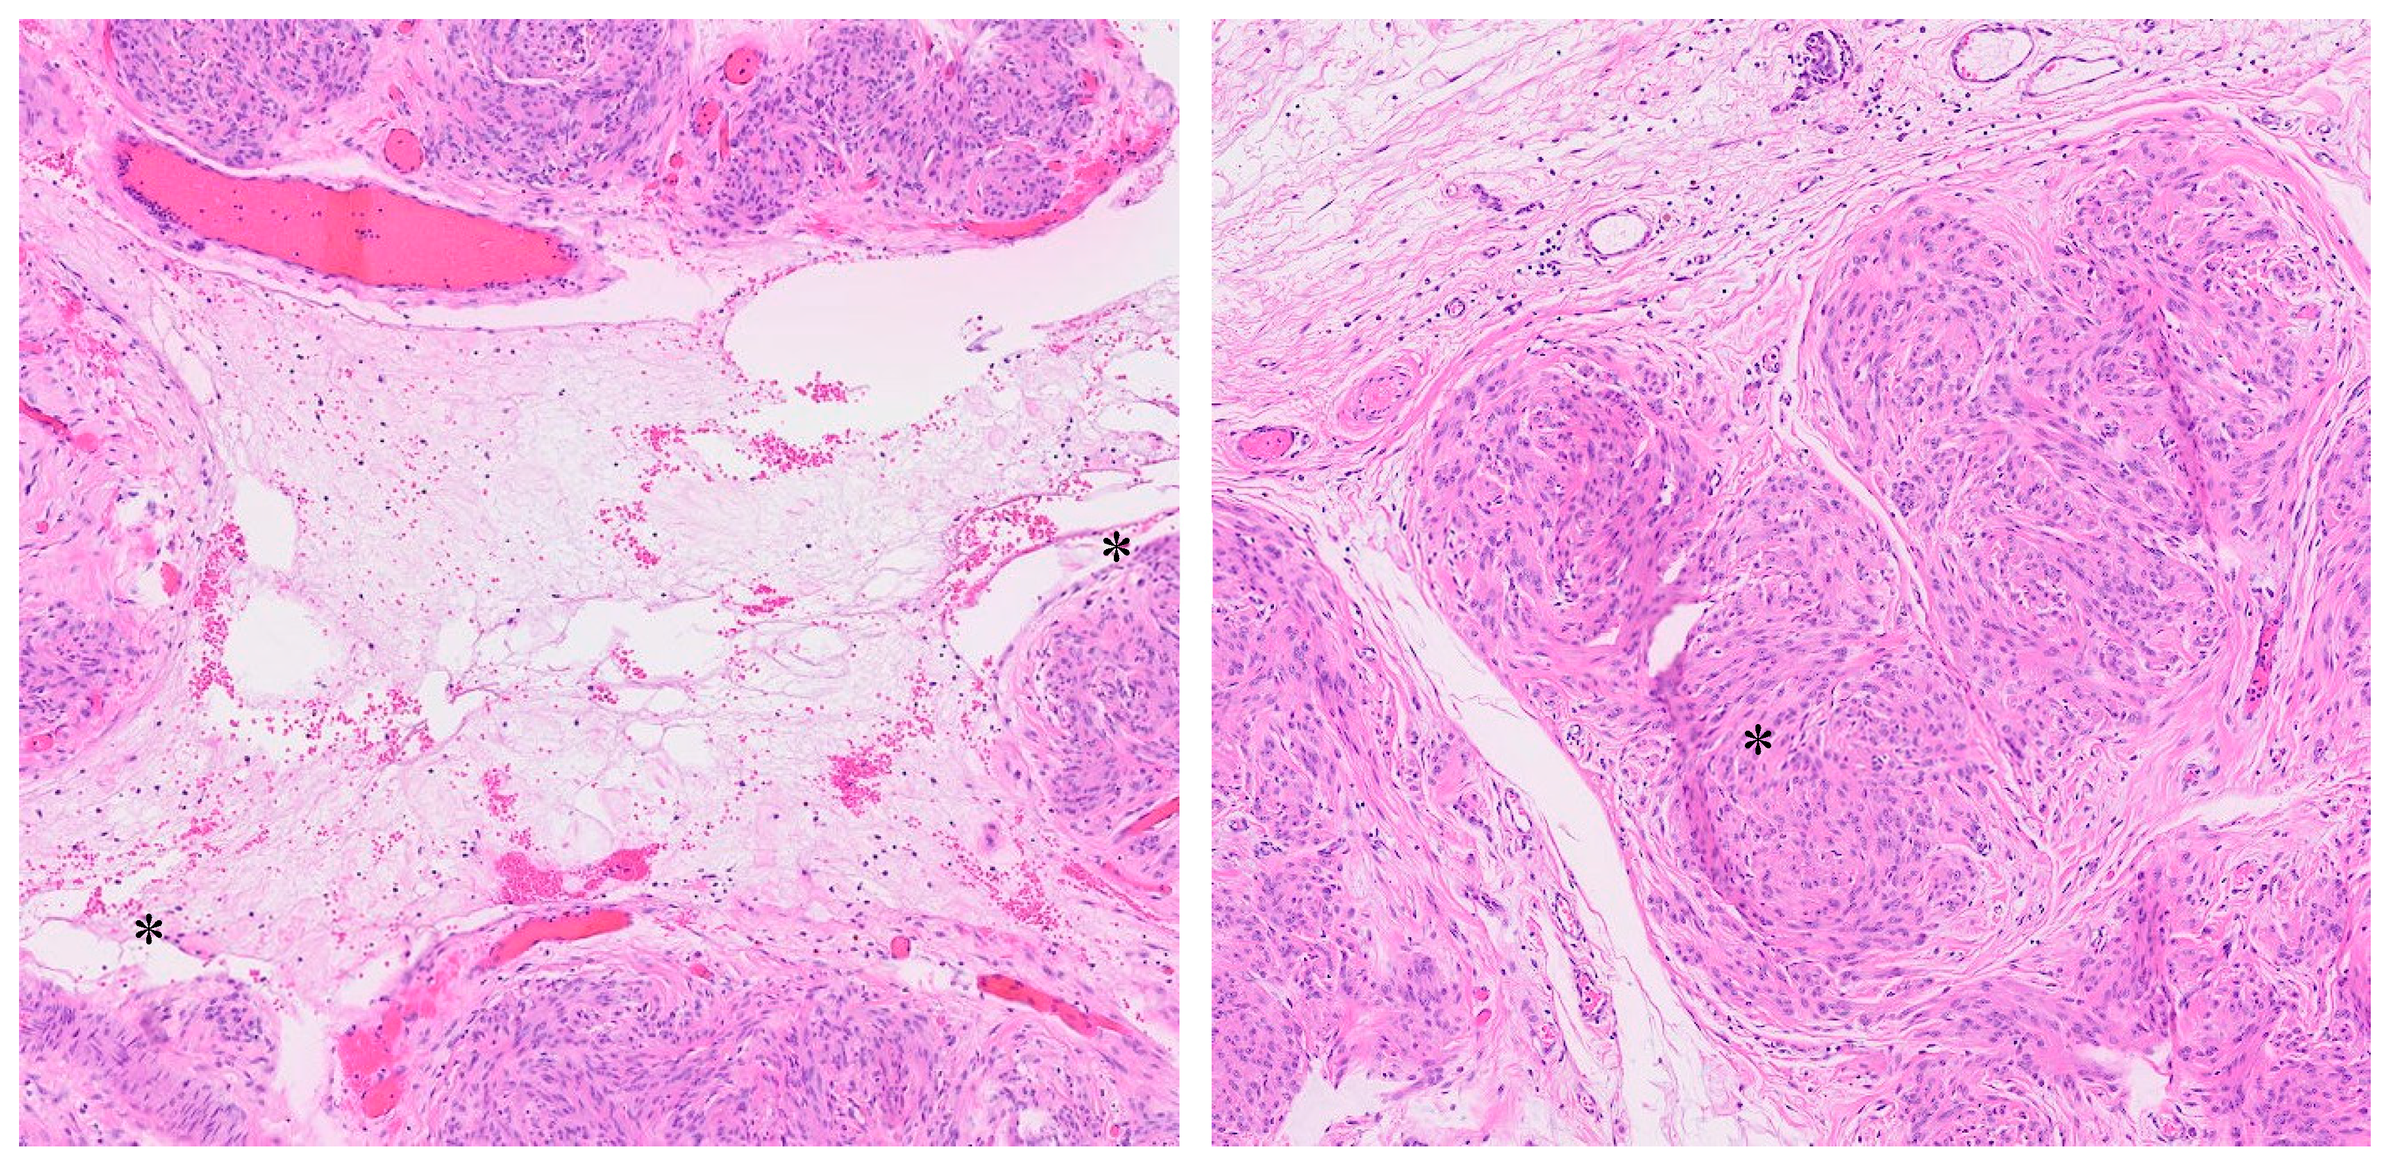

3. Histopathology

4.2. Histopathology and Differential Diagnosis

- Clement, P.B.; Young, R.H.; Scully, R.E. Diffuse, perinodular, and other patterns of hydropic degeneration within and adjacent to uterine leiomyomas. Problems in differential diagnosis. Am. J. Surg. Pathol. 1992, 16, 26–32. [Google Scholar] [CrossRef]

- Coad, J.E.; Sulaiman, R.A.; Das, K.; Staley, N. Perinodular hydropic degeneration of a uterine leiomyoma: A diagnostic challenge. Hum. Pathol. 1997, 28, 249–251. [Google Scholar] [CrossRef]

- Smith, C.C.; Gold, M.A.; Wile, G.; Fadare, O. Cotyledonoid dissecting leiomyoma of the uterus: A review of clinical, pathological, and radiological features. Int. J. Surg. Pathol. 2012, 20, 330–341. [Google Scholar] [CrossRef]

- Kim, S.-N.; Jang, J.; Kim, K.-R. Uterine Leiomyomas with Perinodular Hydropic Degeneration—A Report of Two Cases. Korean J. Pathol. 2002, 36, 257–261. Available online: https://www.jpatholtm.org/upload/pdf/kjp-36-4-257.pdf (accessed on 23 February 2025).